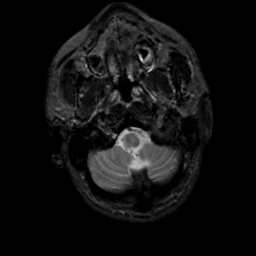

MR Study #5, March 10, 1991 -- Slice #6